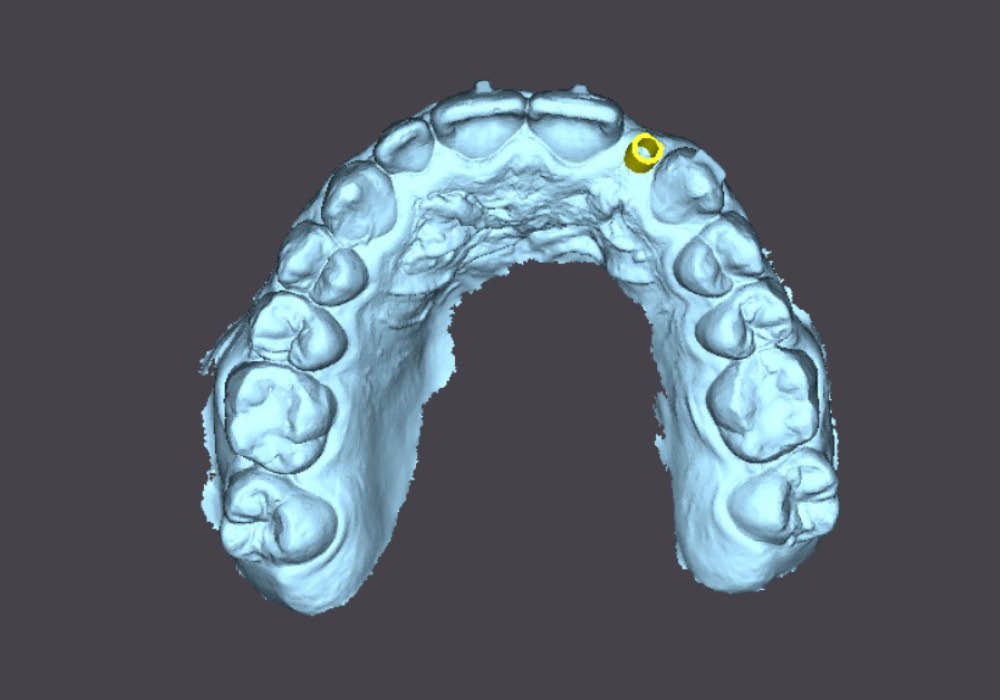

La segmentazione dei dati CBCT è stata effettuata partendo da un file DICOM.

L’utilizzo dell’intelligenza artificiale ha permesso di automatizzare la separazione e la ricostruzione tridimensionale delle strutture anatomiche, facilitando l’elaborazione e garantendo maggiore precisione nella valutazione iniziale.